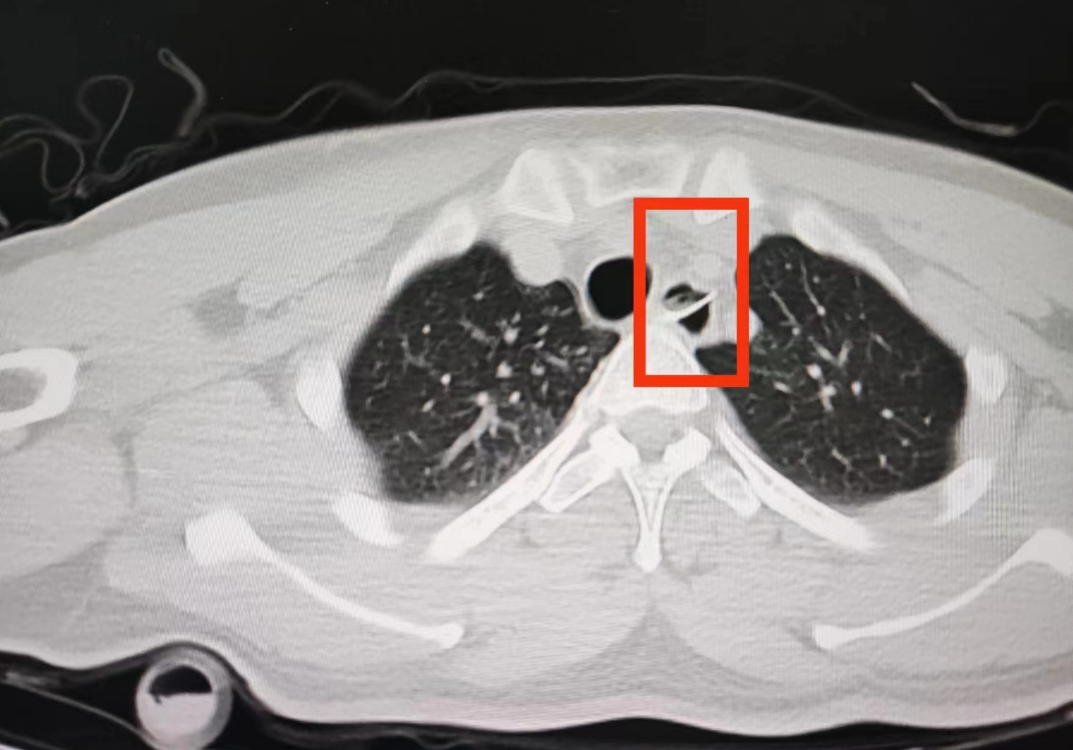

得知小宋喝了酒又吃了鱼,

王宇晨立马安排小宋胸部CT检查,

影像显示小宋的食管被异物穿透了!

原来吃饭时小宋误吞了鱼刺,

直到鱼刺穿透食管才感觉到疼痛。